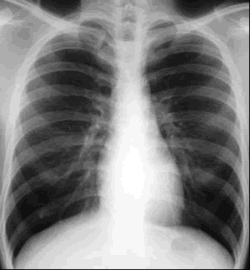

Tuberculosis (TB)

Articles on Tuberculosis